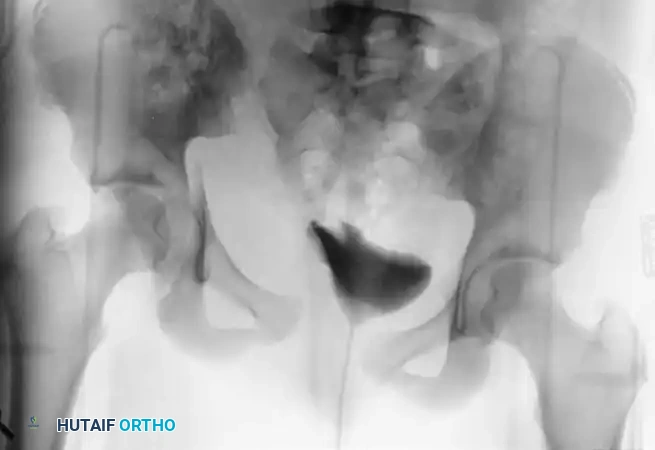

Meticulous preoperative planning requires high-quality orthogonal radiographs (AP, Inlet, and Outlet views) and a fine-cut computed tomography (CT) scan with 3D reconstructions to fully delineate the fracture morphology, assess for occult sacral fractures, and evaluate the sacroiliac (SI) joints.

Reduction Techniques for the Pubic Symphysis

Achieving an anatomical reduction of the pubic symphysis requires a combination of manual traction, specialized clamps, and an understanding of the multiplanar deforming forces.

- Exposure: Place narrow, sharp Hohmann retractors underneath the rectus muscle bellies and over the superior pubic rami to fully expose the symphyseal articulation.

- Clamp Placement: Place a Weber pointed reduction clamp anteriorly onto the body of the pubis.

- Sagittal Plane Control: It is critical that the points of the reduction clamp are placed at the exact same horizontal level on the pubic body. As the clamp is closed, this symmetrical placement ensures that any sagittal plane rotation (flexion/extension of the hemipelvis) is simultaneously reduced.